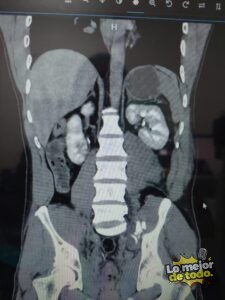

Este tipo de tecnología, que también permite intervenciones como embolizaciones con filamentos de platino y colocación de stents, ya está cambiando vidas. Gómez Moreno recordó un caso reciente: “Un chico cayó de una carreta, que le pasó por el abdomen. Entró en shock por hemorragia interna y, tras varias cirugías, fue nuestro servicio el que permitió ver la arteria que sangraba y sellarla. En una hora estaba estable”.